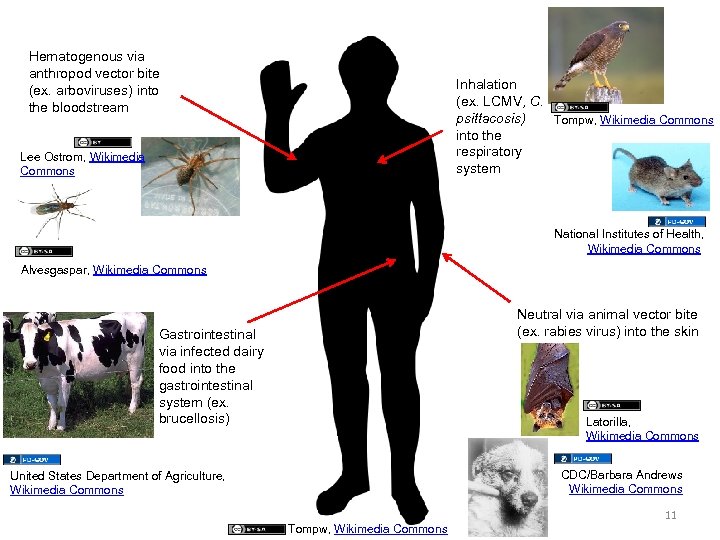

Hematogenous via anthropod vector bite (ex. arboviruses) into the bloodstream Inhalation (ex. LCMV, C. psittacosis) Tompw, Wikimedia Commons into the respiratory system Lee Ostrom, Wikimedia Commons National Institutes of Health, Wikimedia Commons Alvesgaspar, Wikimedia Commons Neutral via animal vector bite (ex. rabies virus) into the skin Gastrointestinal via infected dairy food into the gastrointestinal system (ex. brucellosis) Latorilla, Wikimedia Commons CDC/Barbara Andrews Wikimedia Commons United States Department of Agriculture, Wikimedia Commons 11 Tompw, Wikimedia Commons